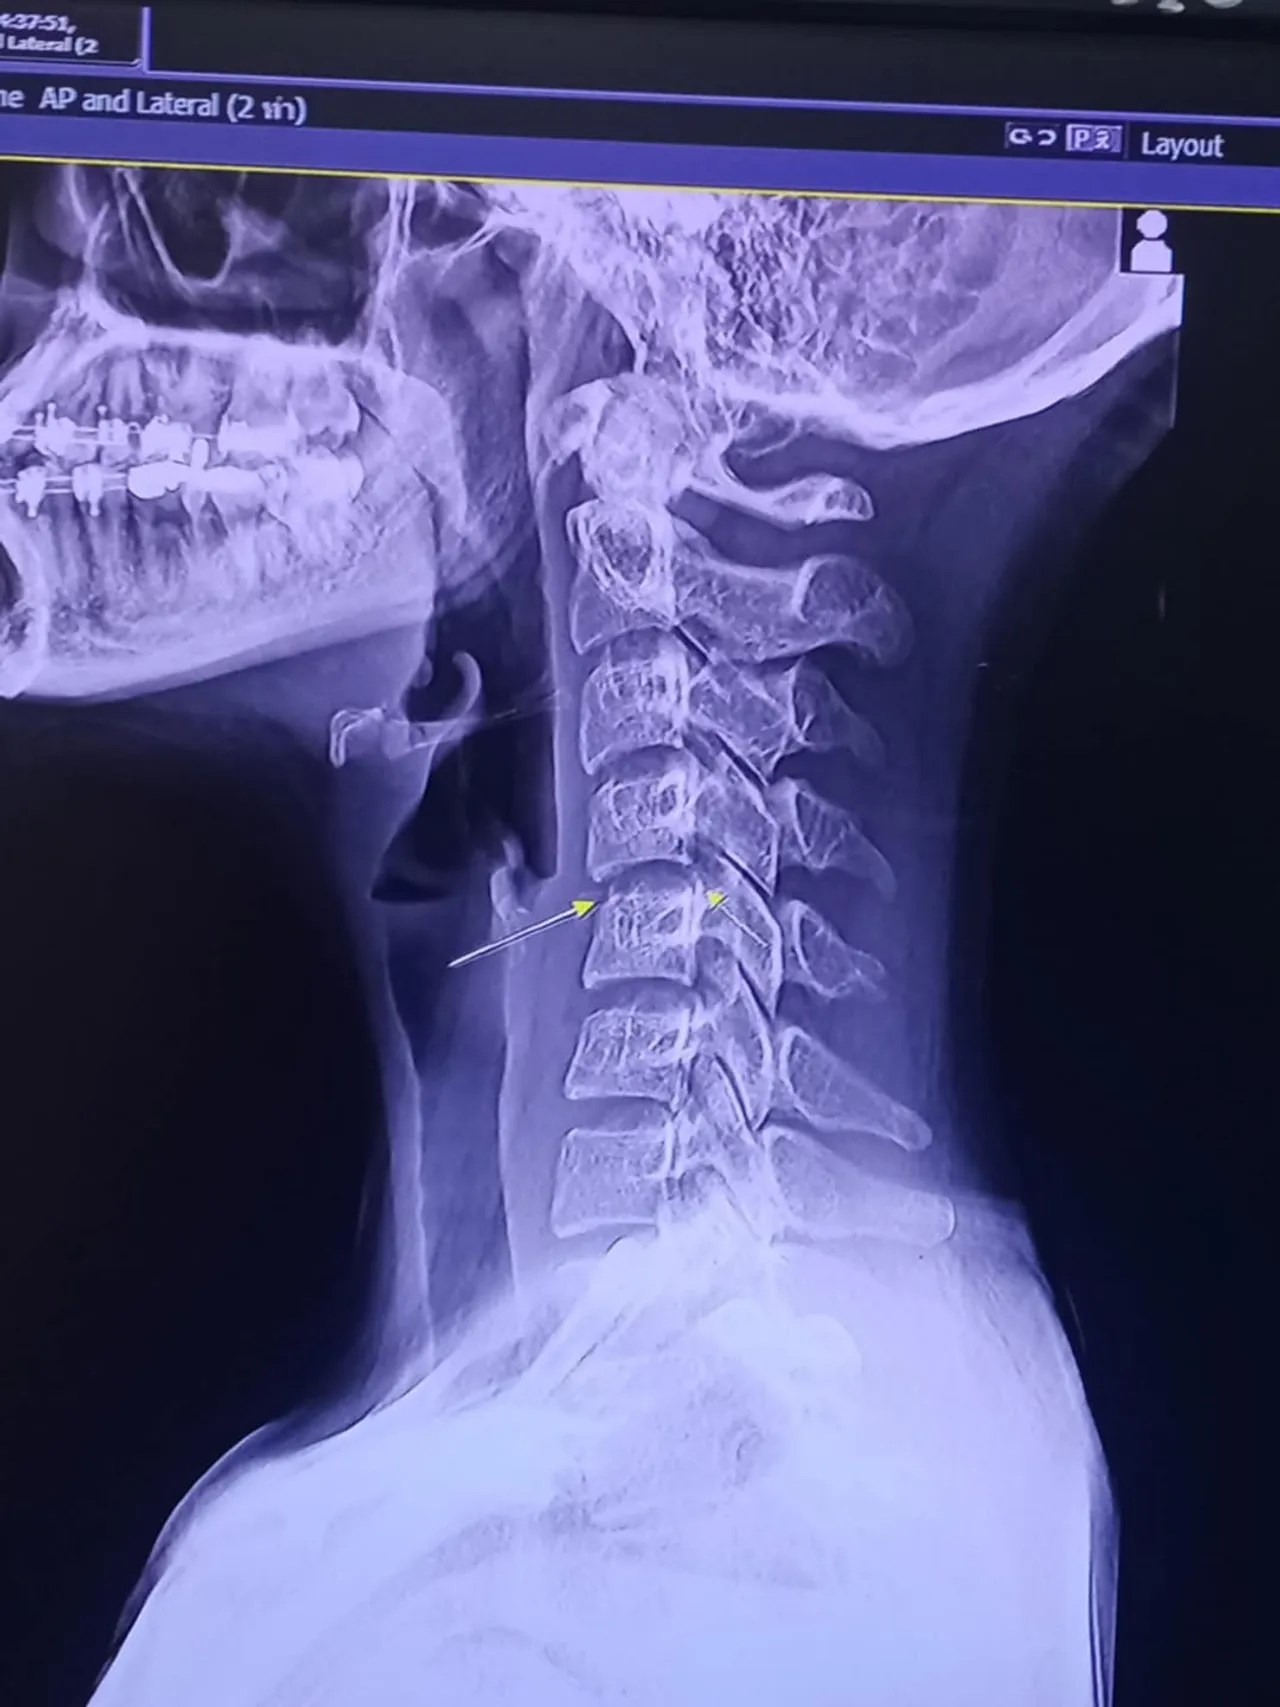

สรุปได้กระดูกคอเคลื่อนกลับมา ทับเส้นประสาทอีก ตาย อาการ แขนกระตุกตลอดเวลา คันทั้งที่ไม่มีตุ่มอะไร ชาครึ่งซีก ตั้งแต่หัวไปเท้า อ่อนแรงยกของไม่ขึ้น (ใส่กางเกงแทบไม่ได้เลยด้วยซ้ำ) ปวดทีลามไปทั้งตัว ทรมานมาก เพราะกระตุกจนทำอะไรไม่ได้เลย ปวดกว่าเดิมอีกตั้งหาก เป็นประสบการณ์ที่แย่มากๆสำหรับคนอายุแค่ 20″